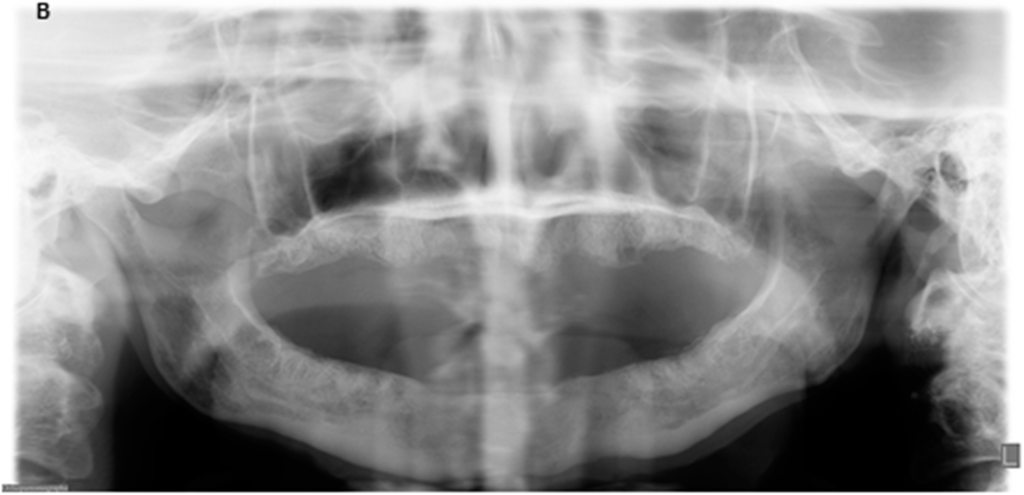

Figure 2.

Radiologic findings before surgery and nine months after surgery. (A) Panoramic radiograph with extensive osteolysis, extending from region 46 to 34 up to the inferior border in the region of the symphyse; (B) Panoramic radiograph nine months post-operatively with healed, smooth edges of the mandibular body.

The panoramic radiograph showed osteolysis of the ventral part of the mandible (Figure 2). The CT scan (Figure 3A) showed massive osteolysis and sequestration of the ventral part of the mandible from region 34 to 45, matching osteomyelitis and BRONJ. The continuity of the mandible seemed intact just because of subperiostal bone formation (Figure 3A).